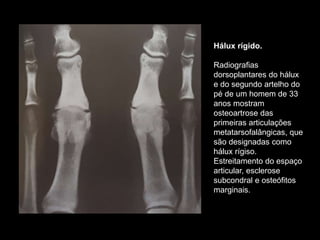

PÉ

• No pé a articulação mais comumente

acometida é a art. Metatarsofalângica do

hálux. Essa condição é designada como

hallux rigidus ou hallux limitus.

Hálux rígido.

Radiografias

dorsoplantares do hálux

e do segundo artelho do

pé de um homem de 33

anos mostram

osteoartrose das

primeiras articulações

metatarsofalângicas, que

são designadas como

hálux rígiso.

Estreitamento do espaço

articular, esclerose

subcondral e osteófitos

marginais.